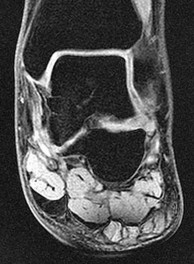

Figures 1a through 1c

Tarsal coalitions occur when primitive mesenchymal cells fail to differentiate and form the

normal articular separations between the tarsal bones of the hindfoot. Overall incidence is difficult to determine because many affected people are minimally symptomatic or asymptomatic. Symptomatic tarsal coalitions typically present in adolescents as a painful flatfoot; however, there are a number of possible presentations, and occasionally symptoms do not appear until adulthood. Most tarsal coalitions are between the calcaneus and the navicular (CN) and the talus and the calcaneus (TC). Although most TC coalitions are across the middle facet, posterior facet coalitions do occur. Plain radiographic evaluation of suspected tarsal coalition is the mainstay for diagnosis. However, coalitions can be bony or fibrous, and making the diagnosis can be difficult. The addition of CT images to distinguish bony definition and MR images to decipher soft tissue can aid in diagnostics. Bony coalitions appear as definite bony bridging between the bones, while fibrous coalitions are suspected when distortion of the bony anatomy is seen. Bony coalitions are best seen on the oblique view (CN) and Harris axial view (TC). There are a number of secondary signs such as the anteater (AE) sign (elongation of the anterior process of the calcaneus as it extends to the navicular as seen on the lateral view [CN]). talar beaking (traction spur of the talar neck thought to result from abnormal stresses as seen on the lateral view [both CN and TN]), and the “C” sign (a continuous cortical contour from the medial talus to the sustentaculum tali [ST]) as seen on the lateral view (TC). A number of newer signs are not as well known, such as a broad mediolateral dimension of the navicular on the anteroposterior (AP) view (the

navicular is wider than the talar head [CN]), nonvisualization of the middle facet on the lateral view (TC), the brick sign (a normal ST is flat, but a distorted ST is enlarged and curved [CN]), and a tapered lateral navicular bone as seen on the AP view (the medial navicular [CN] is much thicker than the lateral navicular).

Figure 1a shows talar beaking (TB), an AE, and an open middle facet (MF). Figure 1b shows a wide navicular (WN), and Figure 1c shows an abnormal articulation between the calcaneus and the navicular, all consistent with a CN coalition.